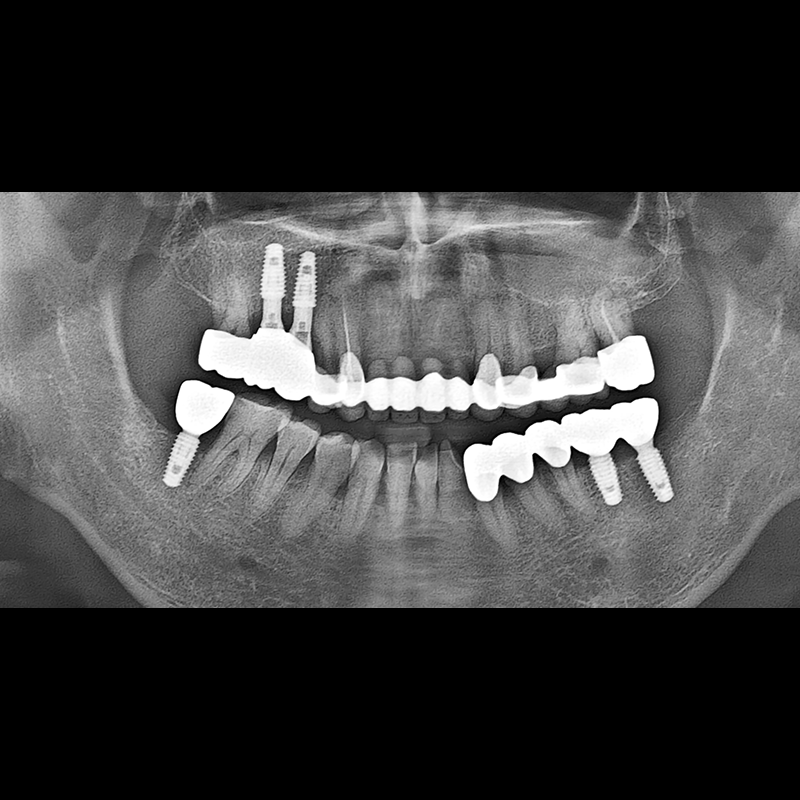

BEFORE AFTER

임플란트 전후사진 2025.05.30

결손된 치아 부분과 살리기 힘든 치아 위치에 임플란트를 식립하였습니다.